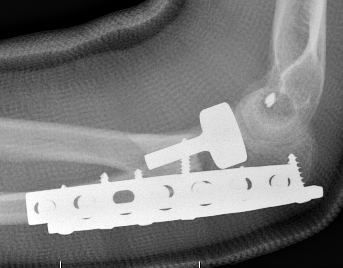

Universal posterior approach

Identify olecranon fracture

- isolate and protect ulna nerve

- dissection out medial and lateral proximal ulna

- reduce and plate olecranon

+/- medial approach for coronoid pocess

- FCU split or elevate entire flexor pronator mass

- identify coronoid process

- small - lasso suture through olecranon

- large - lag screws / buttress plate

Lateral Kocher approach

- +/- ORIF /replace radial head

- +/- repair / reconstruct LCL

+/- hinged fixator

Olecranon plate + ORIF Type II coronoid process + radial head replacement

Olecranon plate with radial head replacement

Olecranon plate with radial head replacement + LCL repair

Olecranon plate + medial coronoid buttress plate + radial head replacement